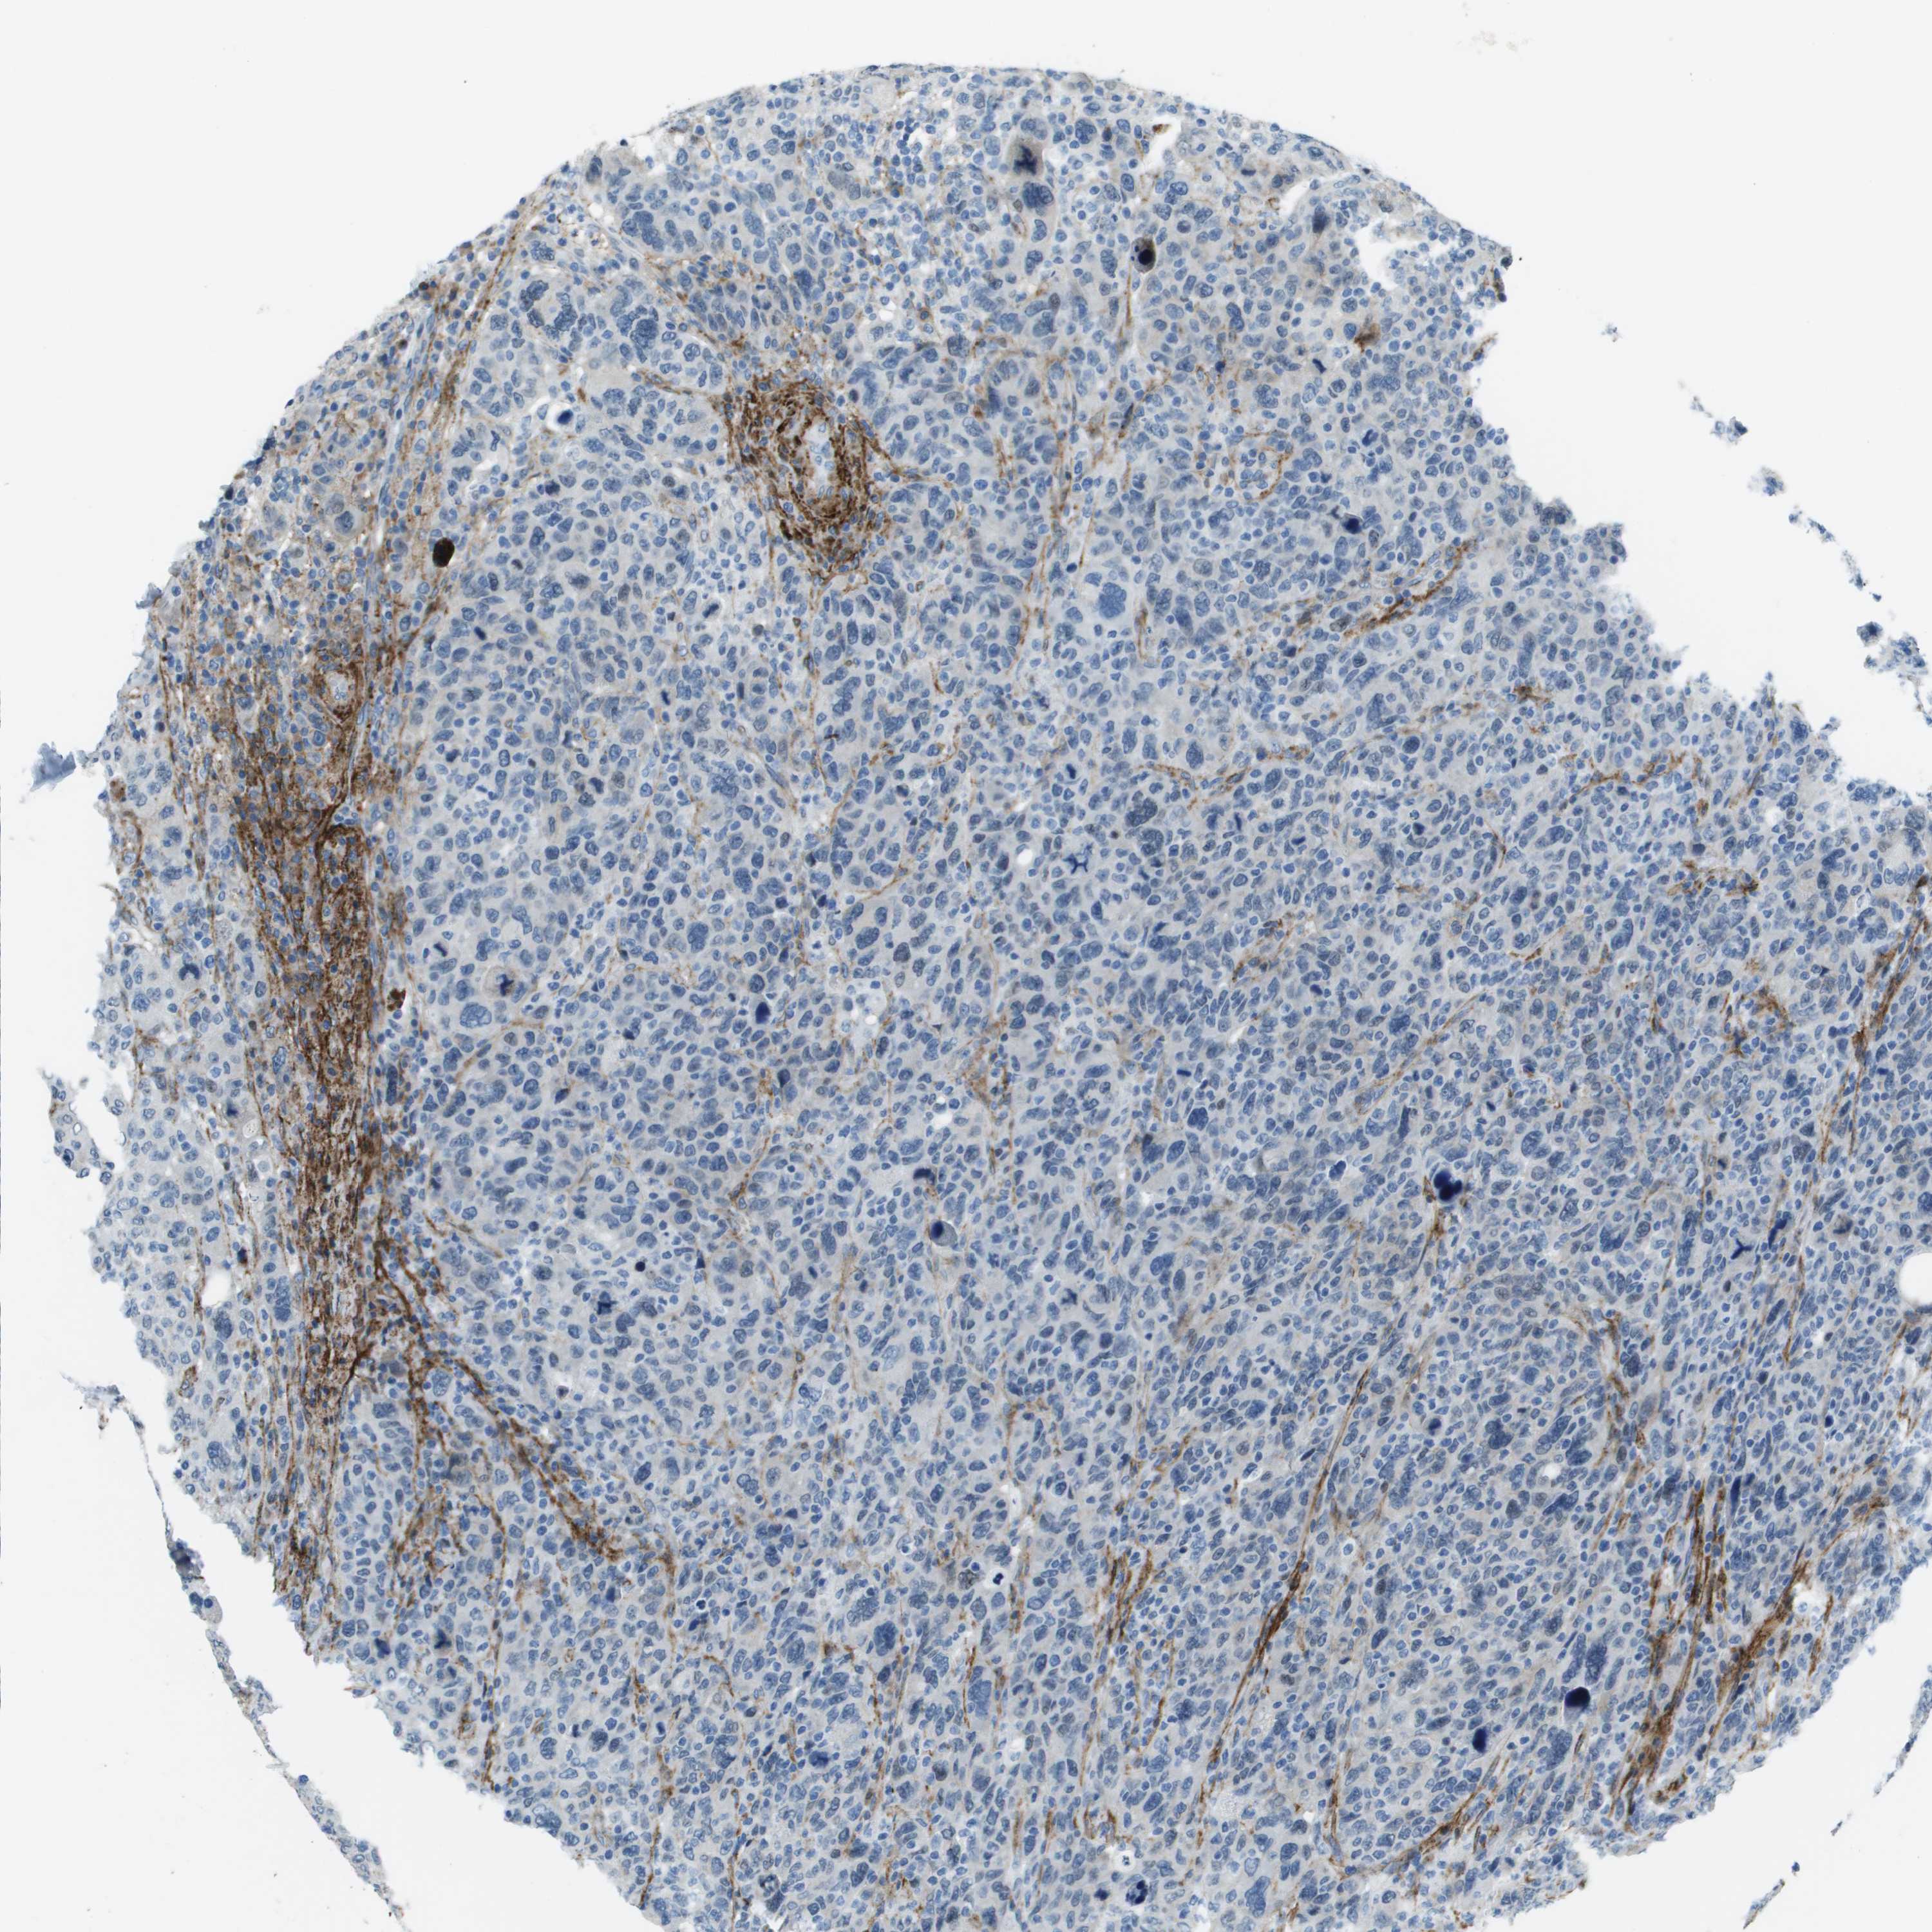

BRCA TCGA BRCA VALIDATION PROTEIN EXPRESSION

Breast cancer

Human cancer